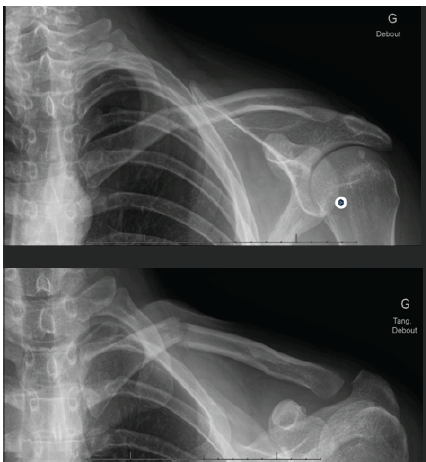

A 23-year-old right-handed male, working in automation and a non-smoker, sustained a skiing accident with direct impact on the left shoulder. Following the trauma, he experienced acute pain and functional impairment of the left upper limb. On the day of the injury, initial clinical and radiological evaluation revealed a slightly displaced closed fracture of the medial third of the left clavicle (Fig. 1).

Figure 1: Radiograph taken at the first consultation, 1 week after the accident.

The patient was treated with orthopedic vest immobilization and analgesic therapy. At the 7-day follow-up, during the clinical and radiological control visit, the patient was no longer wearing the orthopedic vest due to discomfort with immobilization. His condition was as follows: pain was controlled, and physical examination showed swelling at the medial clavicle without signs of skin compromise, tenderness on palpation of the acromioclavicular joint (ACJ) and fracture site, and no signs of horizontal or vertical instability of the distal clavicle. Radiological evaluation showed a slightly displaced fracture of the medial third of the left clavicle with increased angulation compared to the initial radiograph, along with an acromioclavicular distortion and suspected posterior dislocation of the distal clavicle (Rockwood stage IV) on the tangential projection (Fig. 2).

Figure 2: Radiograph taken at the second consultation showing a secondary displacement.